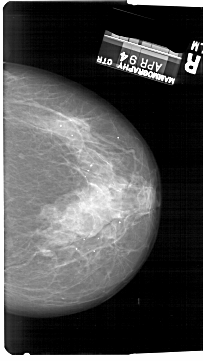

A_1728_1.RIGHT_MLO

RIGHT_MLO LINES 6781 PIXELS_PER_LINE 3976 BITS_PER_PIXEL 12 RESOLUTION 43.5 NON_OVERLAY